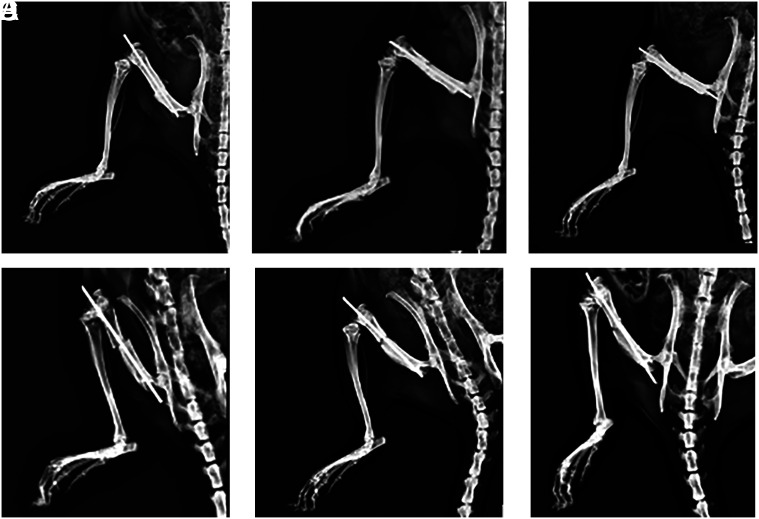

本研究旨在评估法匹拉韦对骨折愈合的影响。48 只雌性大鼠的股骨骨折经 Kirschner 钢丝髓内固定后分为 6 组,其中 2 组为对照组(C1、C2),4 组为实验组(F1、F2、F3、F4)。对照组(C1、C2)口服生理盐水 14 天。其中两个实验组(F1、F2)口服法非拉韦 5 天,其他实验组(F3、F4)口服法非拉韦 14 天。第 14 天,C1、F1 和 F3 组牺牲并进行评估;第 28 天,C2、F2 和 F4 组牺牲并进行评估。采用 Lane 和 Sandhu 评分系统对骨折部位的愈合情况进行放射学评估,并采用 Huo 等人评分系统对骨折部位的愈合情况进行组织学评估。在第 14 天进行的放射学和组织学评估方面,各组之间没有差异(P > .05,P=.216)。第 28 天,对照组的放射学评分明显高于实验组(P < .05)。从组织学角度来看,对照组的骨折愈合情况优于服用了法匹拉韦的组(P < .001)。这项研究表明,无论从放射学还是组织学角度来看,法非拉韦都会对骨折愈合产生负面影响。

The aim of this study was to evaluate the effects of favipiravir on fracture healing. Forty-eight female rats which had a femur fracture with intramedullary Kirschner wire fixation performed were divided into 6 groups; 2 control groups (C1, C2) and 4 experimental groups (F1, F2, F3, F4). The control groups (C1, C2) received physiological saline by oral gavage for 14 days. Two of the experimental groups (F1, F2) received favipiravir by oral gavage for 5 days, whereas the other groups (F3, F4) received it for 14 days. C1, F1 and F3 groups were sacrificed and evaluated on the 14th day, and C2, F2 and F4 groups were sacrificed and evaluated on the 28th day. The fracture sites were assessed for healing radiologically using the Lane and Sandhu scoring system, and assessed histologically using the Huo et al. scoring system. There was no difference between the groups regarding radiological and histological evaluations made on the 14th day (P > .05, P=.216, respectively). On the 28th day, the radiological scores were found to be significantly higher in the control group when compared to the experimental groups (P < .05). Histologically, the control group demonstrated better fracture healing than the groups that had favipiravir administered (P < .001). This study has shown that favipiravir can have negative effects on fracture healing both radiologically and histologically.